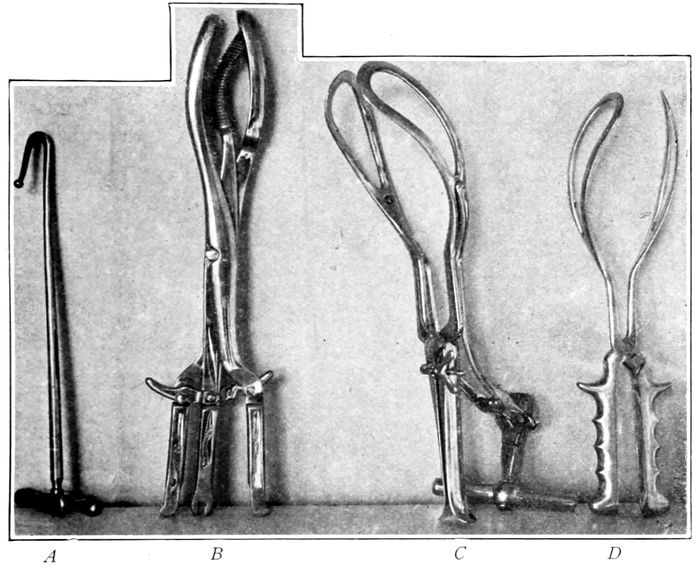

Instruments for artificial delivery of the head |

183 |